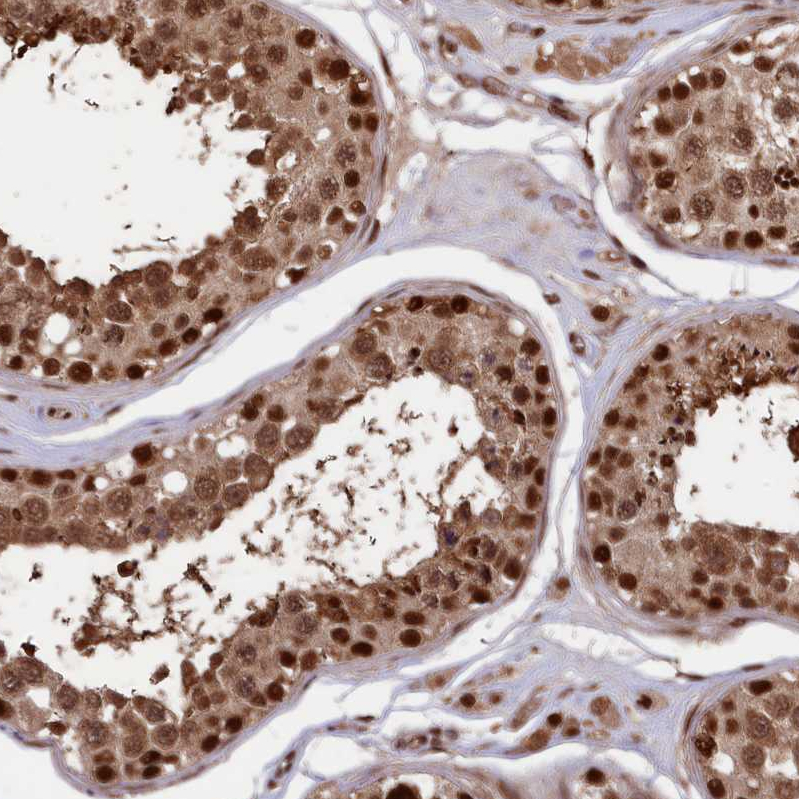

Immunohistochemical staining of human skeletal muscle shows moderate nuclear-cytoplasmic positivity in myocytes.